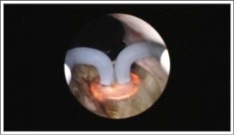

Scionti MRI guided HIFU treatment